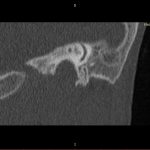

- Diagnosticul traumatismelor de bază de craniu

- Diagnosticul fracturilor:

- Complexe cranio-sinusale

- Complexe cranio-etmoidale

- Complexe cranio-orbitare

- Complexe cranio-faciale